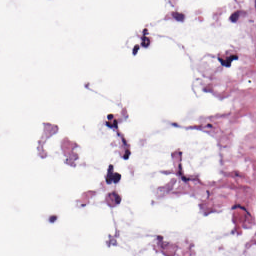

wsi.read_region(

coord, patch_level, (patch_size, patch_size)).convert('RGB')

从上面的结果,我们可以知道,Whole_Slide_Bag_FP 这个函数的作用就是使用之前存下来的patch的坐标信息,在整个wsi图片上进行裁减,最后得到若干张固定大小和固定通道的patch